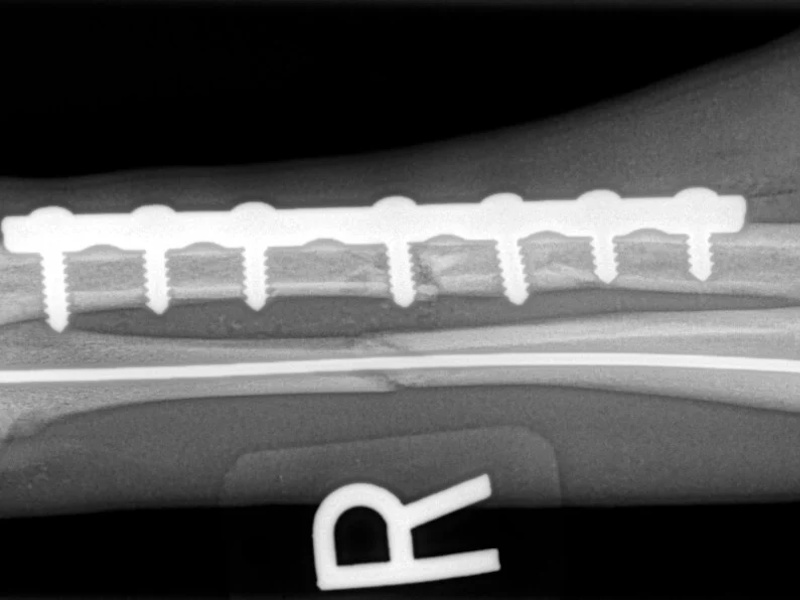

An osteotomy is a surgical cut in a bone. In the cruciate deficient stifle, a cut is made in the top of the tibia. The top portion of bone that contains the articular surface is rotated to level it. The two pieces of bone are held in place with a metal plate and screws.

While the patient is still anesthetized, the patient is taken into radiology for post-surgery radiographs (X-rays). The radiographs are assessed to measure the new tibial plateau angle. We are aiming for 5-6 degrees relative to the long axis of the tibia. The apparatus (plate and screws) are assessed for size and appropriate position.

Fore Limb (Humerus, Radius/Ulnar, Metacarpus)

Hind Limb (Pelvis, Femur, Patella, Tibia/Fibula, Lateral Malleolus)